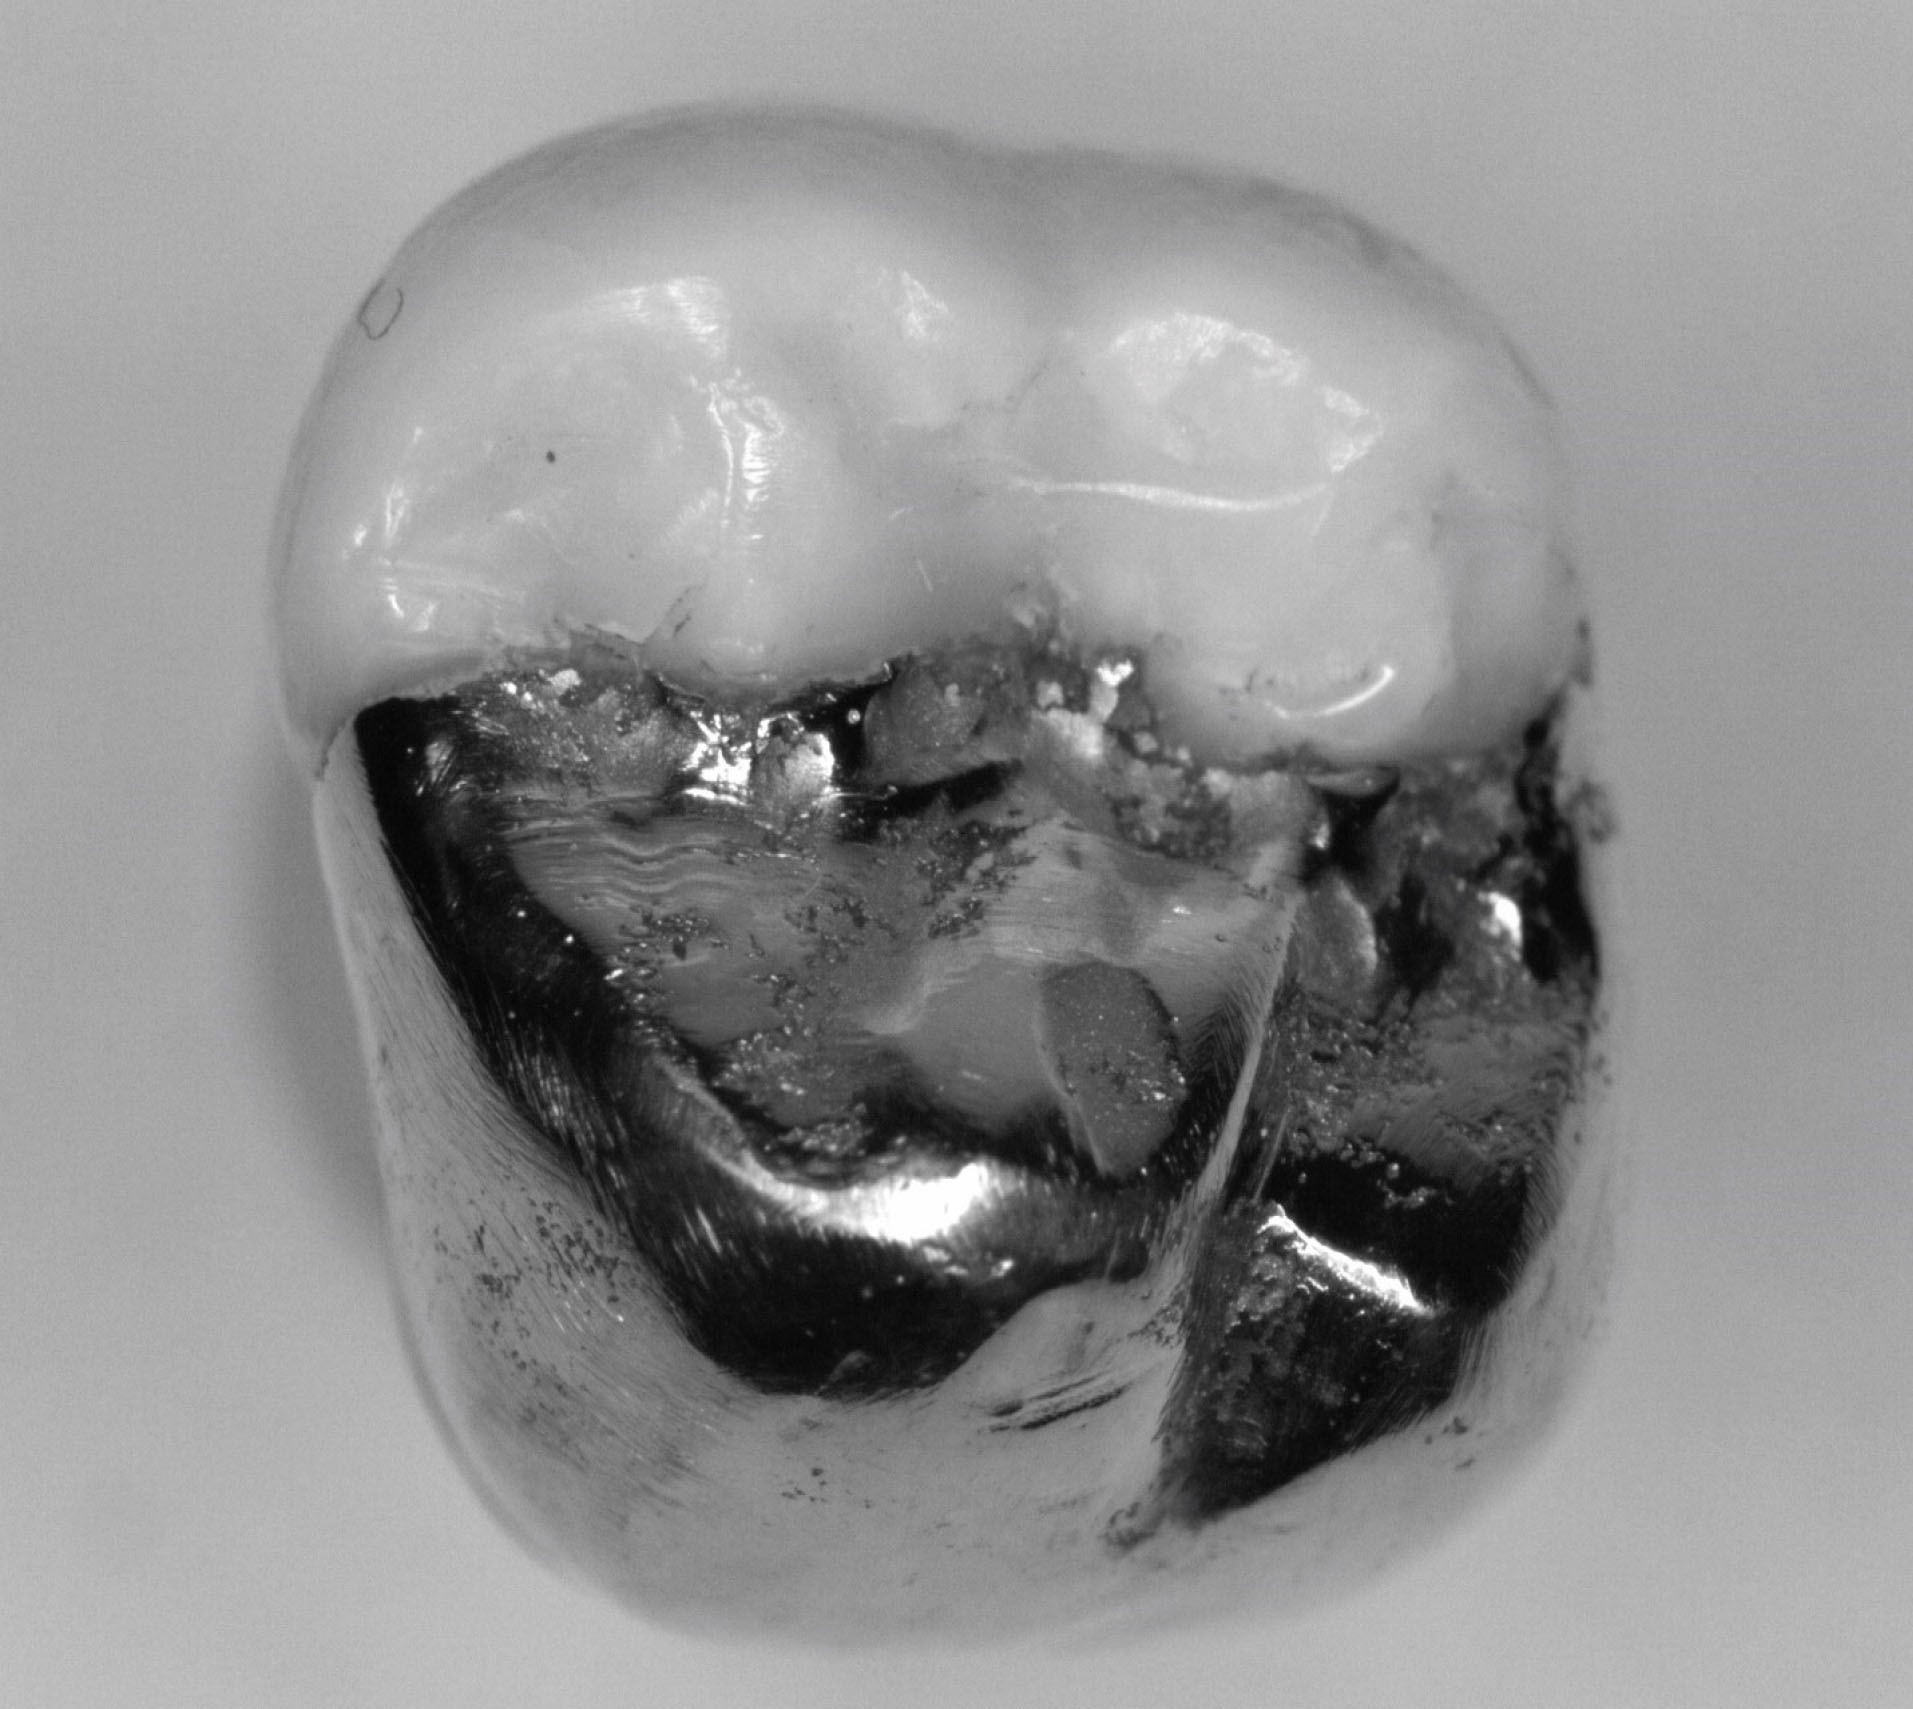

Each onlay was bonded to its corresponding prepared tooth using resin cement (GC, Alsip, United States) following the manufacturer’s protocol. 5 The restorations were then polished with high-speed diamond burs and slow-speed finishing discs. Post-cementation photographs were taken of the restorations in buccal, lingual, mesial, distal and occlusal views ( and ). Radiographs were also taken for each restoration in mesiodistal and buccolingual aspects ( and ).

joddd-15-147-g007

Figure 7. Photograph of the occlusal view of cemented onlay.

The digital scanner provided an STL file of suitable resolution for three-dimensional (3D) printing in metal. The indirect onlay restorations were successfully 3D-printed in cobalt-chromium with dimensions, morphology, and fit clinically acceptable for subsequent cementation. Cementation was unremarkable and adequately retained the onlays, similar to previous investigations. 6 Marginal adaption was generally acceptable but was clinically unacceptable in one area due to an open margin. The surface finish was generally acceptable but could be improved in some areas, especially on the occlusal surface.